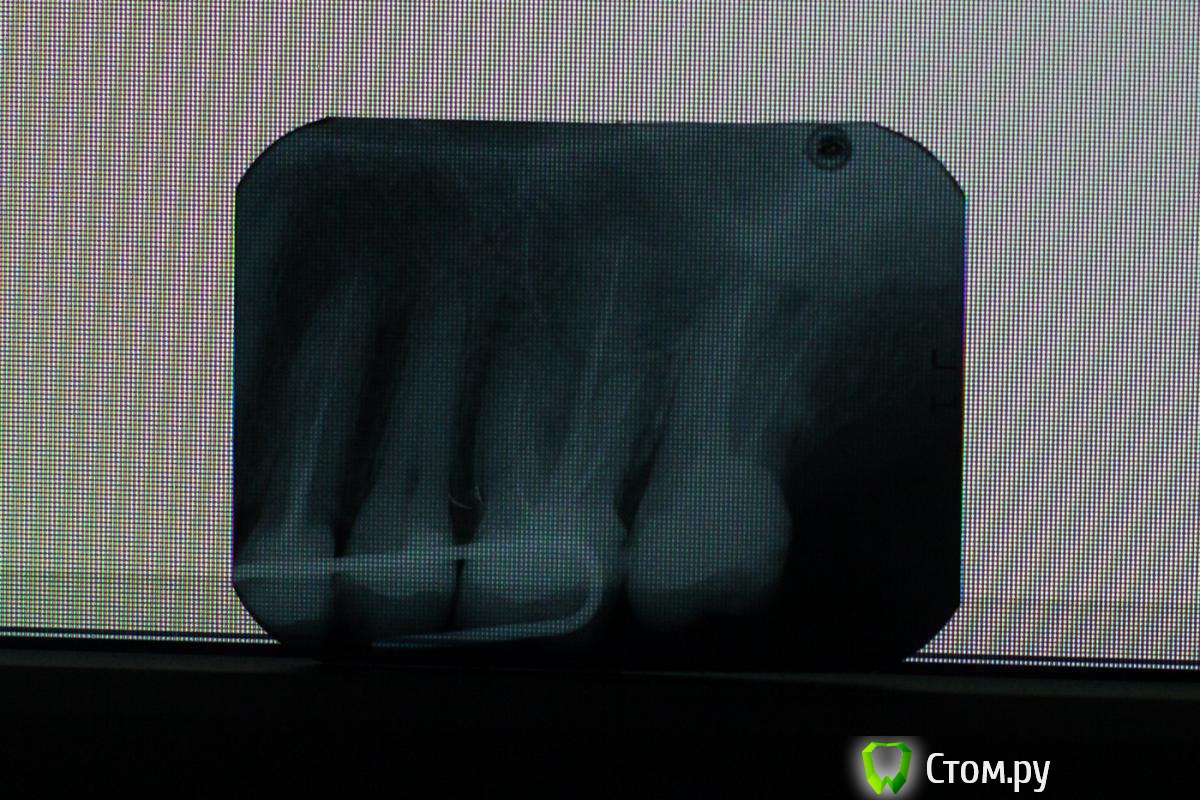

Maruca23 Опубликовано 25 апреля, 2014 Автор Поделиться Опубликовано 25 апреля, 2014 Выложите пожалуйста снимок сфотканный на белом листе бумаги, которая прислонена к окну (при дневном свете) С удовольствием помог бы разобраться Спасибо, вот перефотографировала.. Ссылка на комментарий

Maruca23 Опубликовано 25 апреля, 2014 Автор Поделиться Опубликовано 25 апреля, 2014 вот может так... Ссылка на комментарий

Scrabble Опубликовано 25 апреля, 2014 Поделиться Опубликовано 25 апреля, 2014 (изменено) Четвёртый и шестой перелечить-потом ВКВ и коронки. Не исключён пульпит пятого-надо его проверить. Обратитесь в платную клинику к толковому врачу-он поможет. Изменено 25 апреля, 2014 пользователем Scrabble 1 Ссылка на комментарий

DokDent Опубликовано 26 апреля, 2014 Поделиться Опубликовано 26 апреля, 2014 Отек появился в день,когда зуб заболел..перекосило все лицо и до сих пор отек не спал. У меня на каждом зубе стоит пломба, кариес или пульпит.. все зубы леченые -перелеченные за последние несколько лет. То есть есть вероятность,что эту боль дала не шестерка??? а как узнать наверняка? Боль была постоянной и острообразной, когда зуб заболел я и не пыталась на нем жевать,я вообще не ела почти сутки. Но прочитав ваши комментарии стала вспоминать,что последнее время был дискомфорт при надкусывании... Шестёрка могла, но и пятёрка не исключается. Сказать только по снимку,да ещё и не лучшего качества,точно нельзя. Maruca23, сегодня уже 4-е сутки, если Вам не легче,не надо сидеть и ждать. К опытному стоматологу в хорошую клинику! 1 Ссылка на комментарий